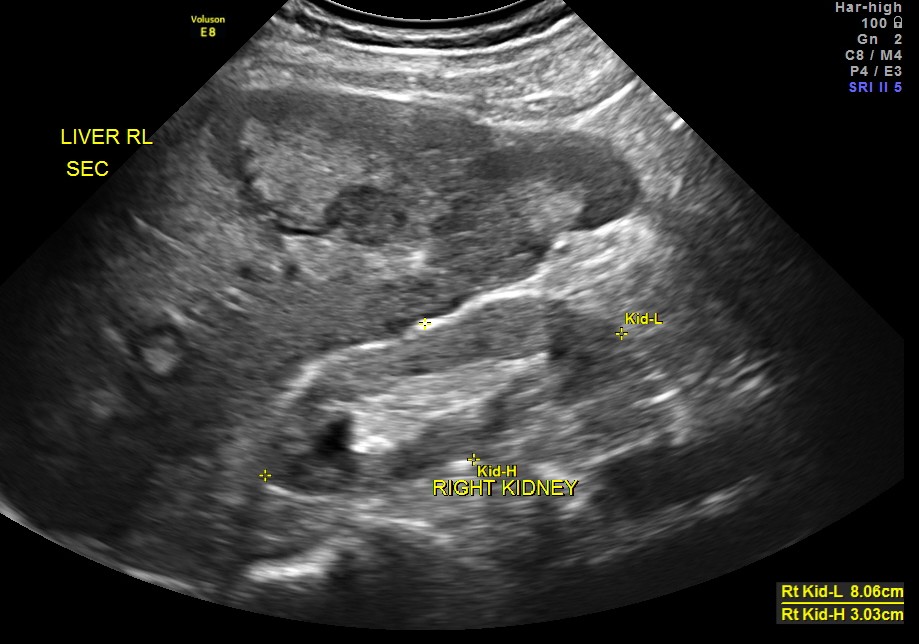

Clinically he had uncontrolled systemic hypertension and mildly elevated s. creatinine of 1.7 mgms/dl.

The diagnosis offered was multiple liver secondaries with incidental finding of shrunk right kidney with probable reduced function.